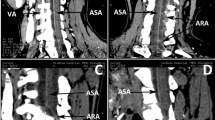

The vertebral artery and the cervical spine are closely related anatomically, but damage to that vessel in cervical spinal injury and subsequent stroke involving the vertebrobasilar distribution has rarely been reported. A case of vertebrobasilar stroke following traumatic injury to the cervical spine is described. The anatomy of the vertebrobasilar system is reviewed and possible mechanisms of injury discussed. A literature review follows.